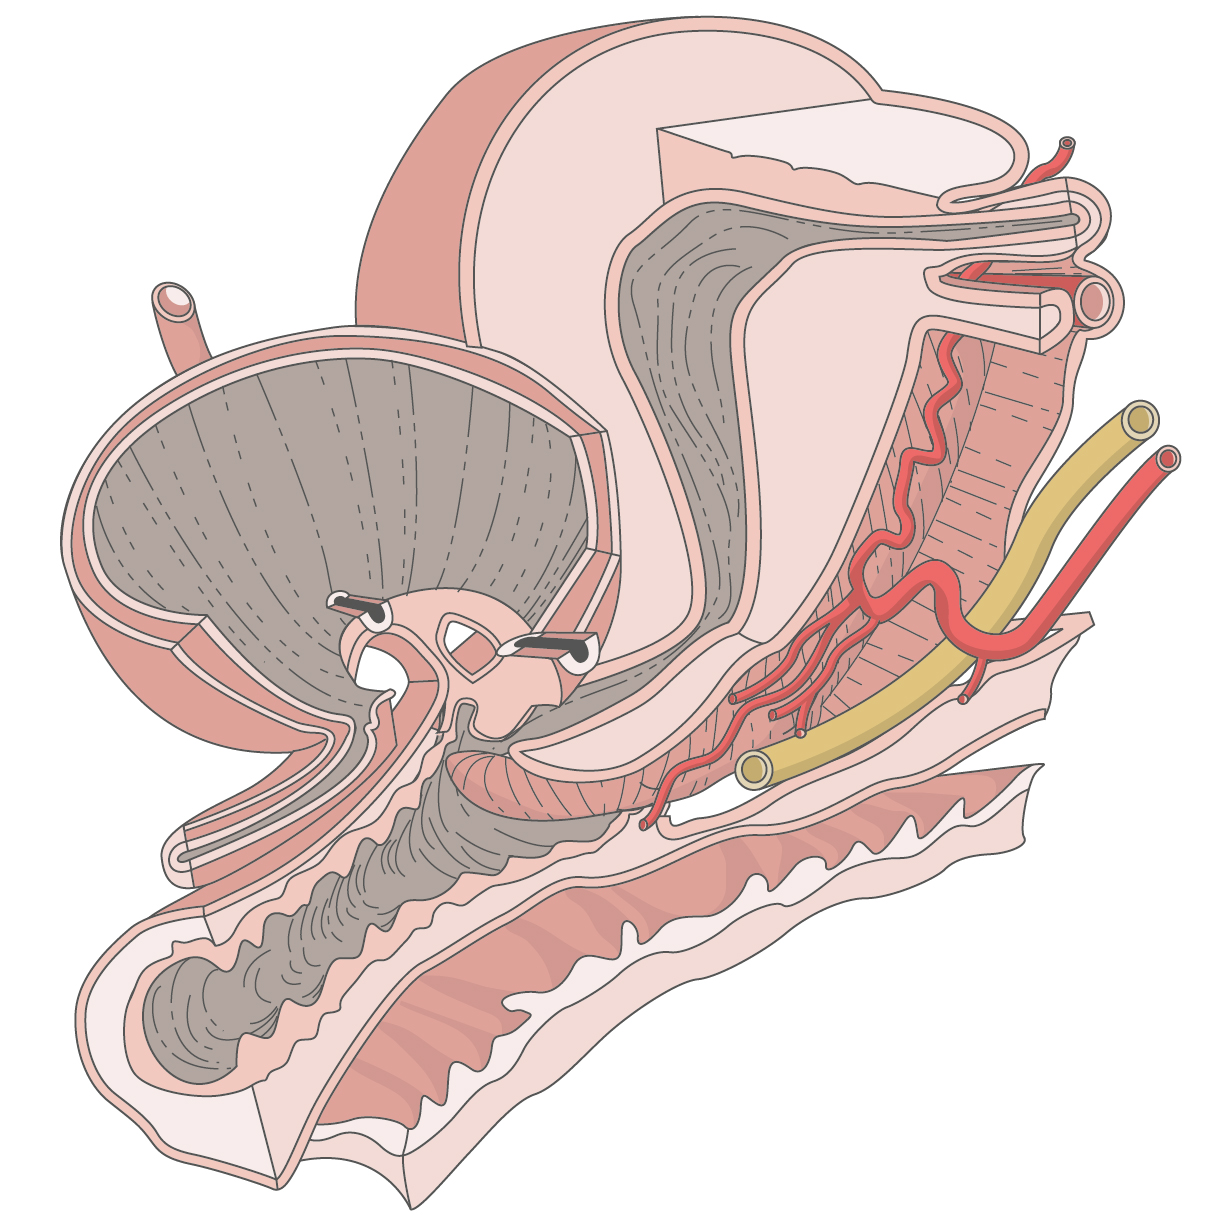

Medizinische Zeichnungen und Kinderbuch Illustration

Herzlich willkommen! Ich bin Ihre Expertin für medizinische Illustrationen und kreative Kinderbuch-Illustrationen. Mit einem Auge für wissenschaftliche Genauigkeit und einer Liebe zur Gestaltung kindgerechter Erzählwelten schaffe ich Bilder, die informieren und begeistern. Entdecken Sie mein Portfolio und lassen Sie sich von meiner Arbeit überzeugen!